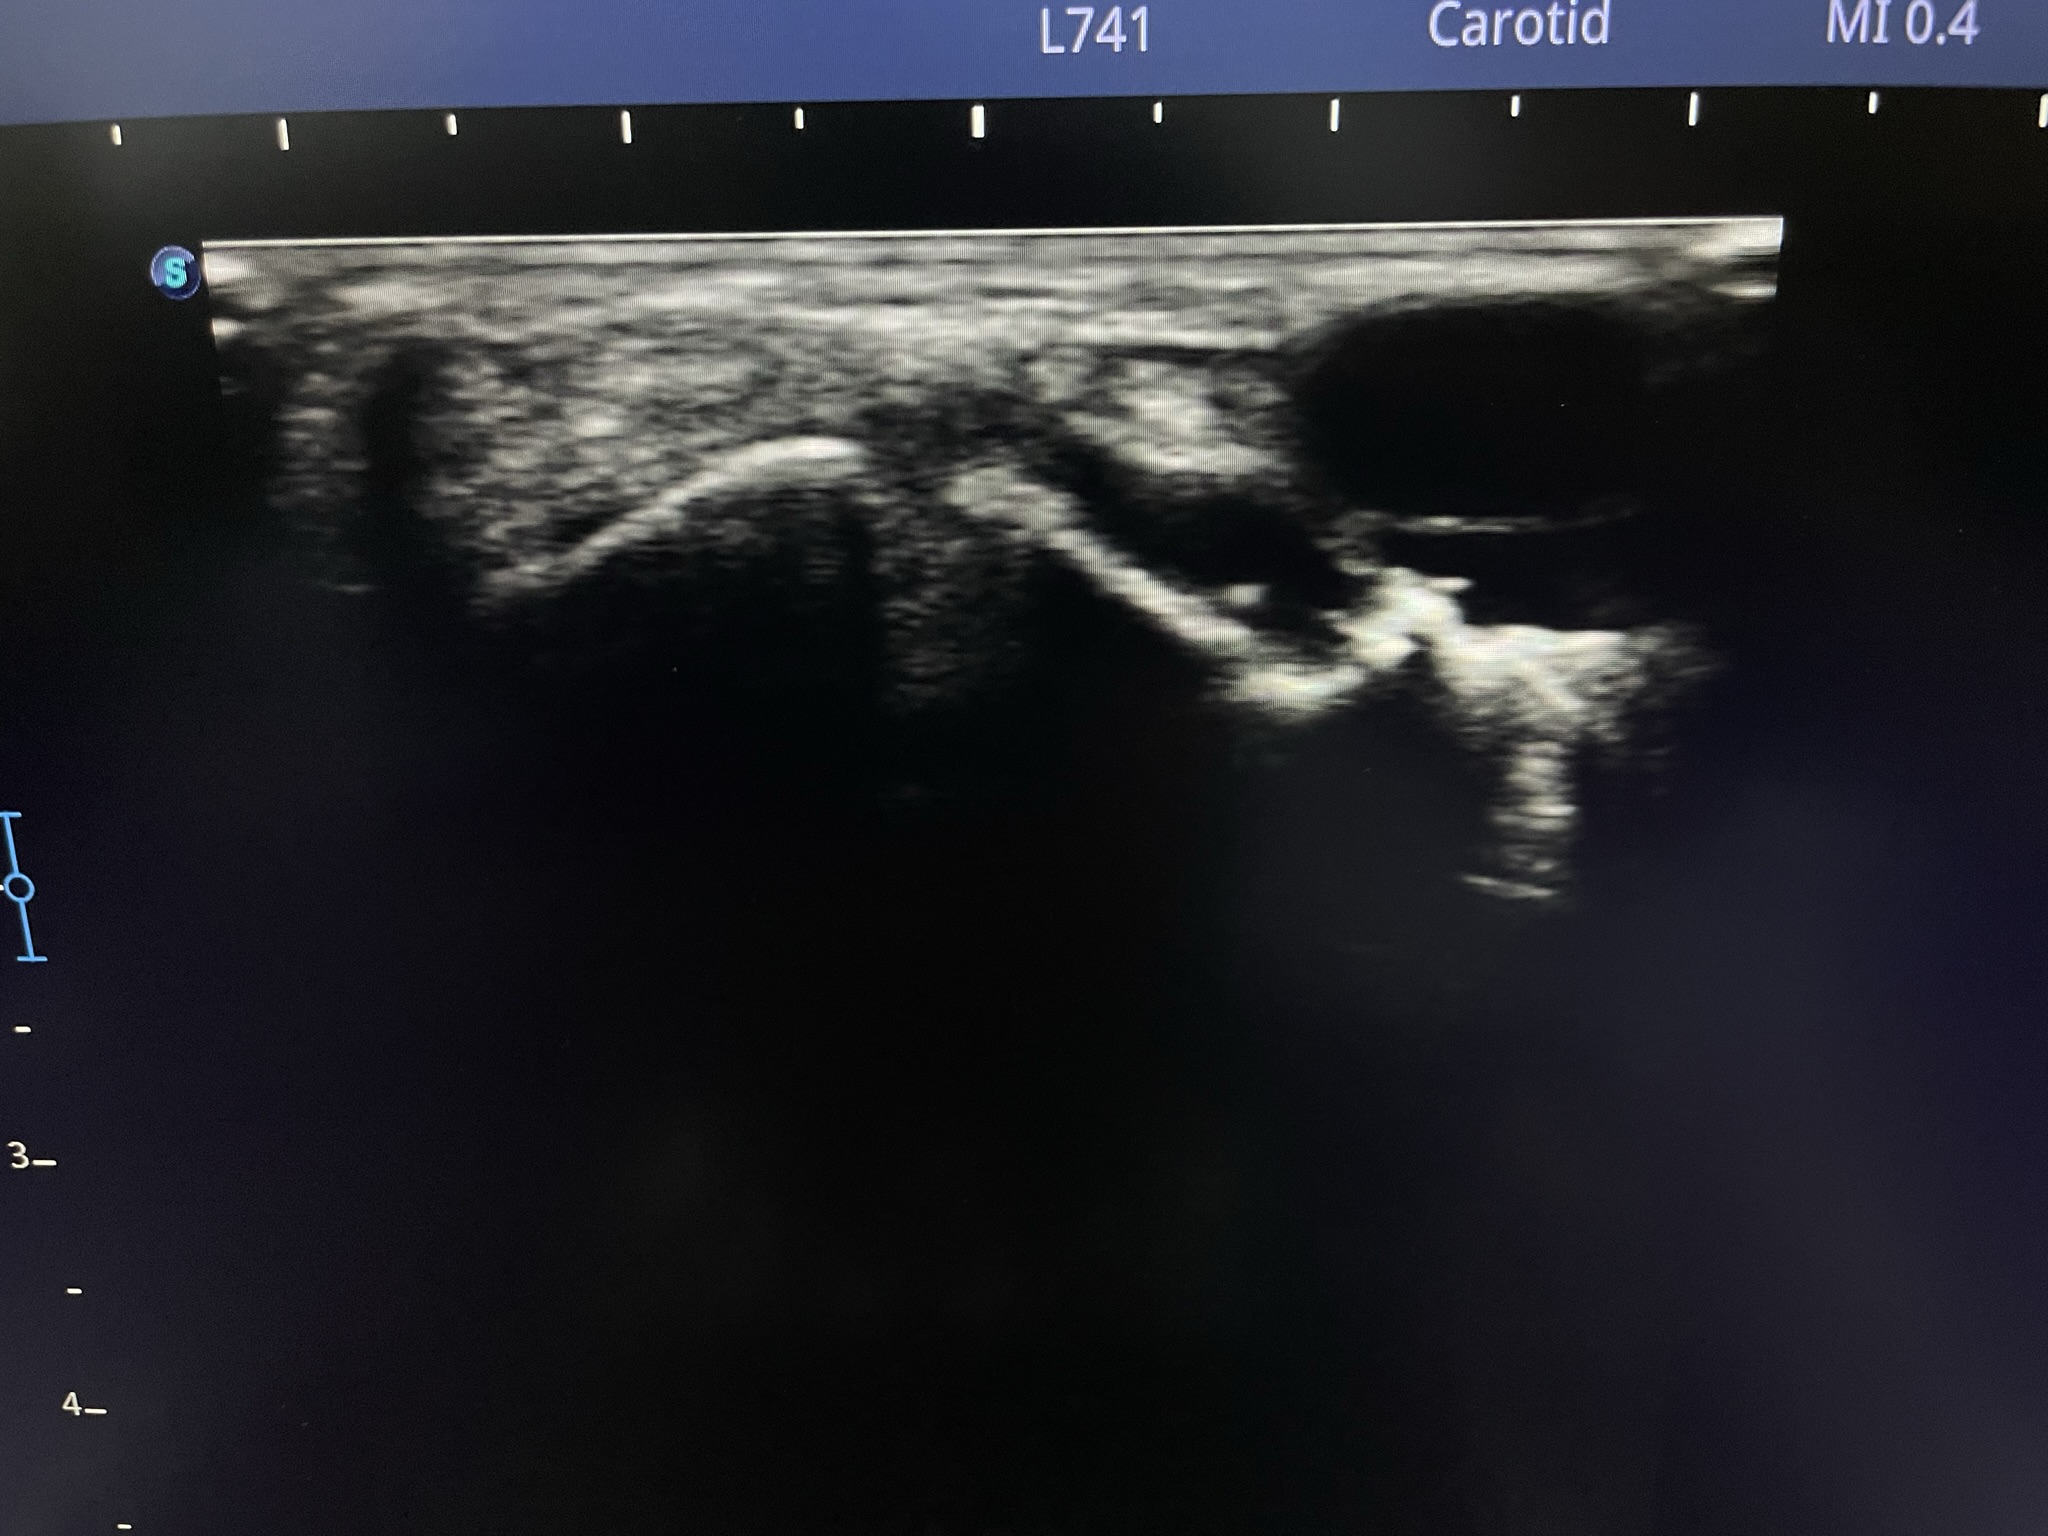

Клинический случай: тыльная гигрома запястья

Пациент с тыльной гигромой, подтверждённой на УЗИ. Выполнено хирургическое лечение, документированы этапы контроля и результаты.